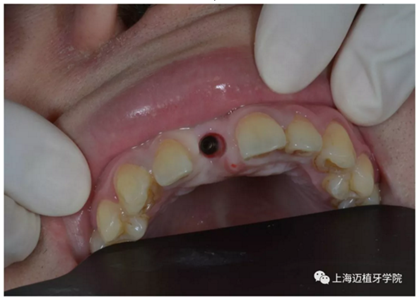

3月后恢復(fù)良好,上愈合基臺

2周后袖口成形

戴牙前口內(nèi)照片:

去除愈合基臺: